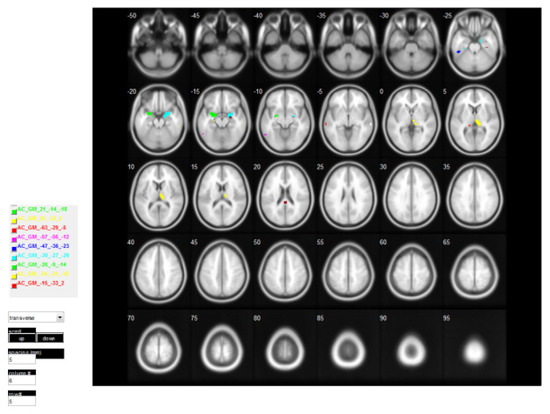

These ROIs are identified based on the t-map generated from VBM analysis. The regions which are significantly different and bundled into the same region are considered as a cluster, as shown in Figure 4, Figure 5 and Figure 6. The generated clusters vary in shape and size, based on the significance of the p-values and the error correction used; p-value was computed based on a repetitive experiment in the range 0.1 to 0.0001, the one with the highest voxel number is reported i.e., p< 0.001. Thus, we have selected for p < 0.001 where 14 clusters were selected out of 30 clusters from the t-map of GM volumes, and one cluster from the t-map of the WM volumes both from the AD and CN two-sample t-tests. Similarly, three clusters were generated from the t-map of the GM volumes of the CN and MCI two-sample t-tests. The selected 18 clusters were used as ROI directly to obtain the mean weighted voxel value from each participating MRI; we will term this ROI as ROI_CL hereinafter. The number of voxels in each ROI_CL differs abruptly so, if we accumulate all the voxels from each ROI, the number of voxels is going to be substantially large; hence one of the logical solutions would be taking mean weighted voxel value as stated in Equation (2) to represent a single value for each selected ROI for each MRI, demonstrated as shown in Appendix A, Table A1.

Each participant’s brain differs in terms of the structure and size of the anatomic regions. This can be more problematic when anatomical ROIs are defined from a single participant and applied to the remaining data, as a significant anatomical inconsistency exists between the participants. Hence, we selected anatomic regions with a higher number of voxels in each cluster. After obtaining those regions, we generated a mask from the automated anatomic labeling (AAL) [34] atlas for those anatomic regions and co-registered with our t-map image. The AAL atlas is a digital human brain atlas with 116 labelled volumes indicating macroscopic brain structures. Hence, these masks can be used subsequently for feature extraction. The most significant regions of the brain based on the t-map image using AAL atlas labels are tabulated in Table 2 and Table 3 for the ADNI and the GARD test conditions, respectively. From the tables, 14 anatomic regions were selected, and the standard ROIs were generated from the AAL atlas, as shown in Figure 7. We will term this ROI as ROI_AAL hereinafter. We applied the same weight-based mean calculation to obtain the mean features to represent each ROI value from all MRI, as in ROI_CL, a few demonstrated as in shown in the Appendix A, Table A2.

For VBM-based ROI, the selection was done manually based on cluster size, ROI_CL, for which we selected the cluster with the highest number of voxels, e.g., AD vs. CN voxels result from the ADNI dataset t-test yielded 30 clusters, of which we selected 14 clusters with significant voxel numbers, while rest small-sized clusters were neglected (please refer to the Supplementary Data file ADNI_AD_CN_p0.001_FWE_BrainLabels). Similarly, the remaining four clusters were selected from the AD vs. CN WM t-test and CN vs. MCI t-test (please refer to the Supplementary Data file ADNI_CN_MCI_p0.001_FWE_BrainLabels). For ROI_AAL the selected clusters were matched with the AAL template, to obtain significant anatomic regions, then those standard ROIs were used to create the mask for further voxel detection from each ROI, for feature detection. On initial matching 23 ROI from AD vs. CN (16 GM and seven WM), nine ROIs from AD vs. MCI, and 11 ROIs from CN vs. MCI were detected. We selected the one with the highest number of voxels from each cluster and the overlapped regions. In total there were 18 ROIs from the cluster and 14 ROIs from the AAL atlas, as shown in Figure 6 and Figure 7, which were tested separately to obtain the best classification result.

Table A1. ADNI-based ROI_CL feature sample data for first three MRIs from each cohort, read as AC_GM cluster at [−46.5 −36.0 −22.5] AC meaning AD vs. CN else CM meaning CN vs. MCI, GM stated the obtained ROI is from gray matter else WM meaning White matter, coordinates indicate its center location.

Location/AC_GM cluster at [−15.0 −33.0 1.5]AC_GM cluster at [−24.0 −21.0 −15.0]AC_GM cluster at [−25.5 −9.0 −13.5]AC_GM cluster at [−30.0 −27.0 −25.5]AC_GM cluster at [−46.5 −36.0 −22.5]AC_GM cluster at [−57.0 −55.5 −12.0]AC_GM cluster at [−63.0 −28.5 −4.5]AC_GM cluster at [15.0 −31.5 1.5]AC_GM cluster at [21.0 −13.5 −18.0]AC_GM cluster at [25.5 −9.0 −13.5]AC_GM cluster at [30.0 −27.0 −25.5]AC_GM cluster at [37.5 −22.5 −27.0]AC_GM cluster at [64.5 −24.0 −6.0]AC_GM cluster at [64.5 −31.5 −16.5]AC_WM cluster at [1.5 −36.0 21.0]CM_GM cluster at [−27.0 −10.5 −13.5]CM_GM cluster at [13.5 −31.5 1.5]CM_GM cluster at [27.0 −9.0 −15.0]Target class/Label

Table A2. ADNI-based ROI_AAL feature sample data for first three MRIs from each cohort, read as rAmygdala_L_f_img, r meaning the region of Amygdala, _L indicating Left region, else R indicating Right region, img for image. Please refer [34] for the coordinate location of each ROIs.

LocationrAmygdala_L_f_imgrAmygdala_R_f_imgrFusiform_L_f_imgrHippocampus_L_f_imgrHippocampus_R_f_imgrInsula_L_f_imgrParaHippocampal_L_f_imgrParaHippocampal_R_f_imgrTemporal_Inf_L_f_imgrTemporal_Inf_R_f_imgrTemporal_Mid_R_f_imgrTemporal_Pole_Sup_L_f_imgrThalamus_L_f_imgrThalamus_R_f_imgTarget class/Label